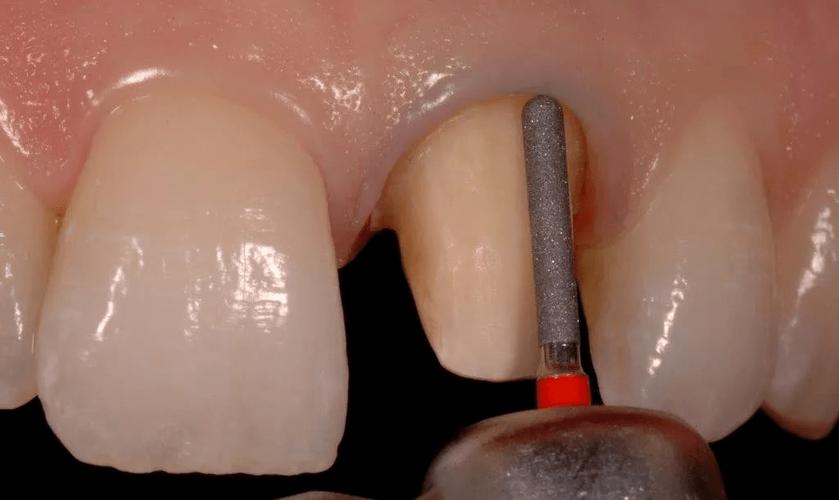

- 预备工具:锥形车针(如878号)、肩台磨光车针。

- 先在牙颈部预备出1.0mm宽的直角肩台雏形;

- 用锥形车针在肩台表面磨出45°-135°的斜面,斜面宽度为肩台宽度的1/2-2/3;

- 斜面与轴壁移行处圆钝,避免形成锐角。